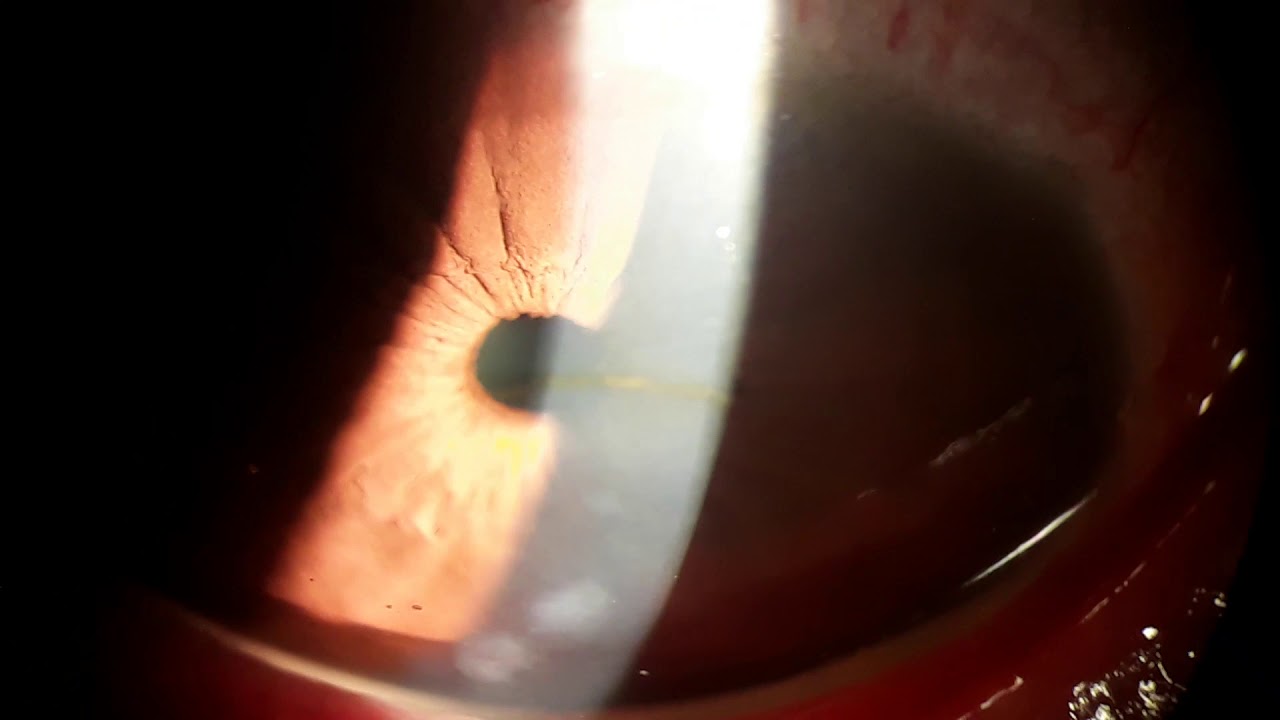

Rizzuti's Sign 이란, 펜라이트 불빛을 비우면 불빛이 각막의 원뿔에서부터 불빛이 모이면서

홍채의 좌측부분에 삼각형 모양으로 빛이 반사되는데 이러한 모양을 의미합니다.